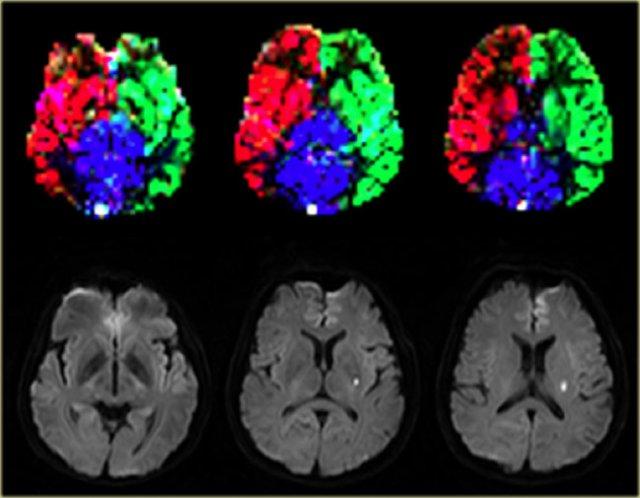

Các biến thể trong vùng tưới máu não có thể được hiển thị bằng kỹ thuật gán nhãn spin động mạch chọn lọc (selective arterial spin-labeling) (9).

Khả năng hiển thị các vùng tưới máu này có vai trò quan trọng trong các nhóm bệnh nhân đặc thù mắc bệnh lý mạch máu não, chẳng hạn như đột quỵ cấp tính, bệnh lý hẹp-tắc động mạch lớn và dị dạng động-tĩnh mạch, vì nó cung cấp thông tin huyết động học có giá trị.

Bên trái là hình ảnh chụp mạch máu MRI theo kỹ thuật thời gian bay (time-of-flight MR angiography) của các động mạch nuôi não, thể hiện kế hoạch lập các lát cắt chọn lọc để khảo sát vùng tưới máu của động mạch cảnh trong trái, phải và hệ động mạch đốt sống-nền.

Vùng tưới máu bình thường ở bệnh nhân nhồi máu ổ khuyết. Hình ảnh được cung cấp bởi Jeroen Hendrikse (9)

Bên trái là hình ảnh của một bệnh nhân có nhồi máu ổ khuyết bên trái với các vùng tưới máu bình thường.

Nhồi máu vỏ não thùy trán trái được tưới máu bởi động mạch cảnh trong phải. Hình ảnh được cung cấp bởi Jeroen Hendrikse (9)

Bên trái là hình ảnh của một bệnh nhân có nhồi máu vùng ranh giới (watershed infarct) ở bán cầu trái, đồng thời có nhồi máu vỏ não ở thùy trán trái (mũi tên).

Lưu ý rằng có sự biến thể trong tưới máu não, cụ thể thùy trán trái được tưới máu bởi động mạch cảnh trong phải.

Bên trái là một biến thể khác trong tưới máu não ở bệnh nhân có nhiều ổ nhồi máu được ghi nhận trên hình ảnh khuếch tán (diffusion imaging).

Có một ổ nhồi máu vỏ não nhỏ ở thùy chẩm trái, vùng này được tưới máu bởi động mạch cảnh trong trái (mũi tên).

Lưu ý rằng hệ động mạch đốt sống-nền không tham gia tưới máu cho vùng này.